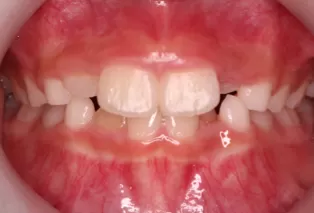

Intraoral photos